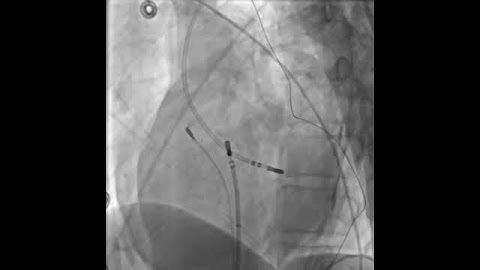

ASPN Virtual Think Tank Session 4: Peripheral Nerve Stimulation and RF Ablation